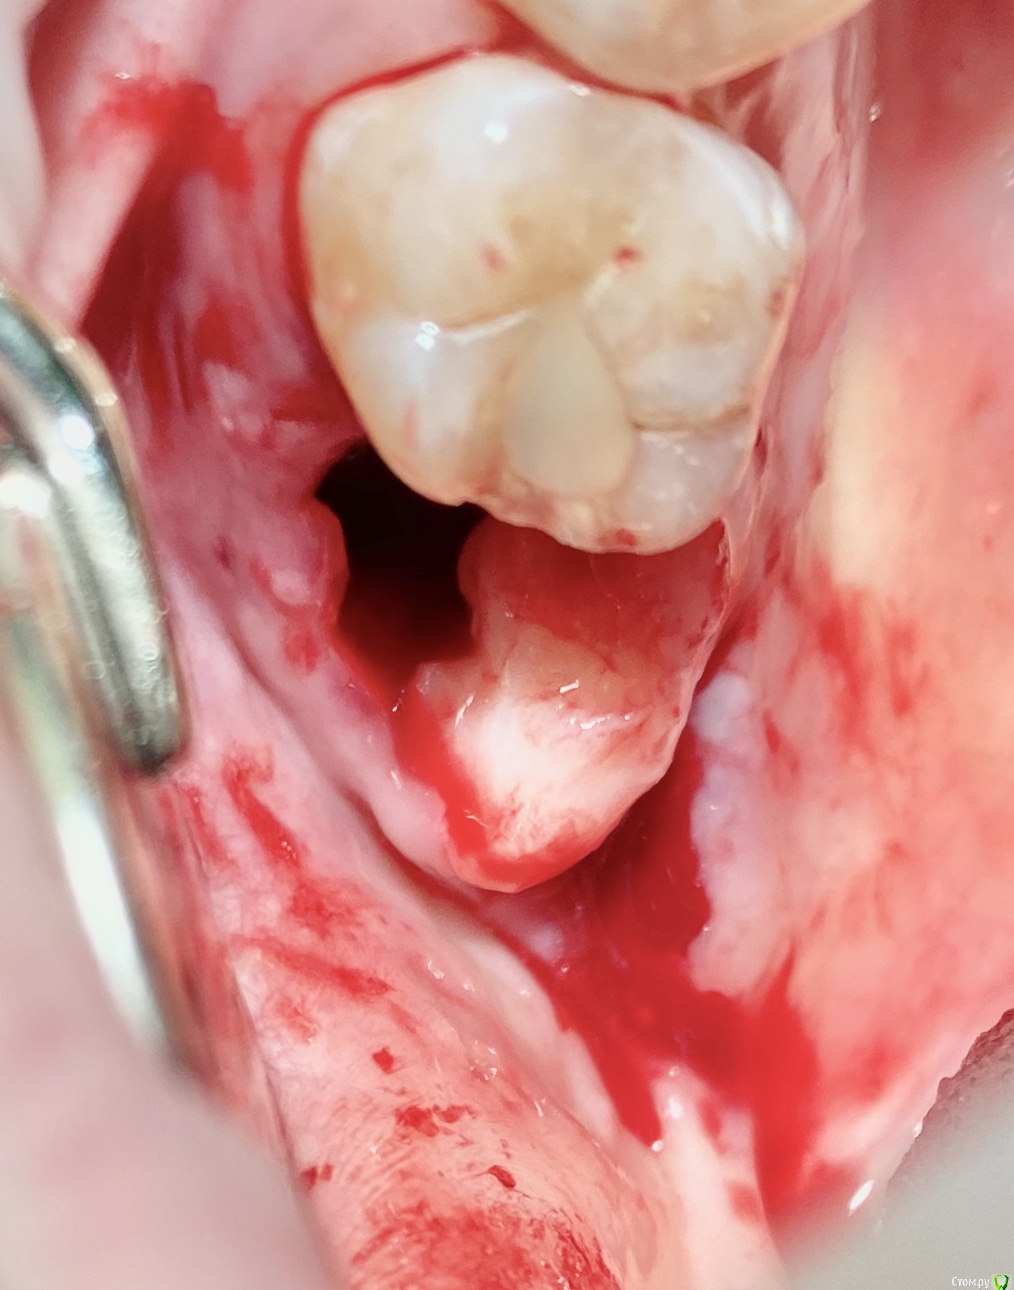

колесников Опубликовано 27 сентября, 2020 Поделиться Опубликовано 27 сентября, 2020 Вид через 2 недели Ссылка на комментарий

Raystom Опубликовано 9 сентября, 2020 Автор Поделиться Опубликовано 9 сентября, 2020 В общем ситуация после пластики не улучшилась, стало чуть хуже. Пока рыхло положил альвостаз, буду смотреть каждые 3 дня Ссылка на комментарий